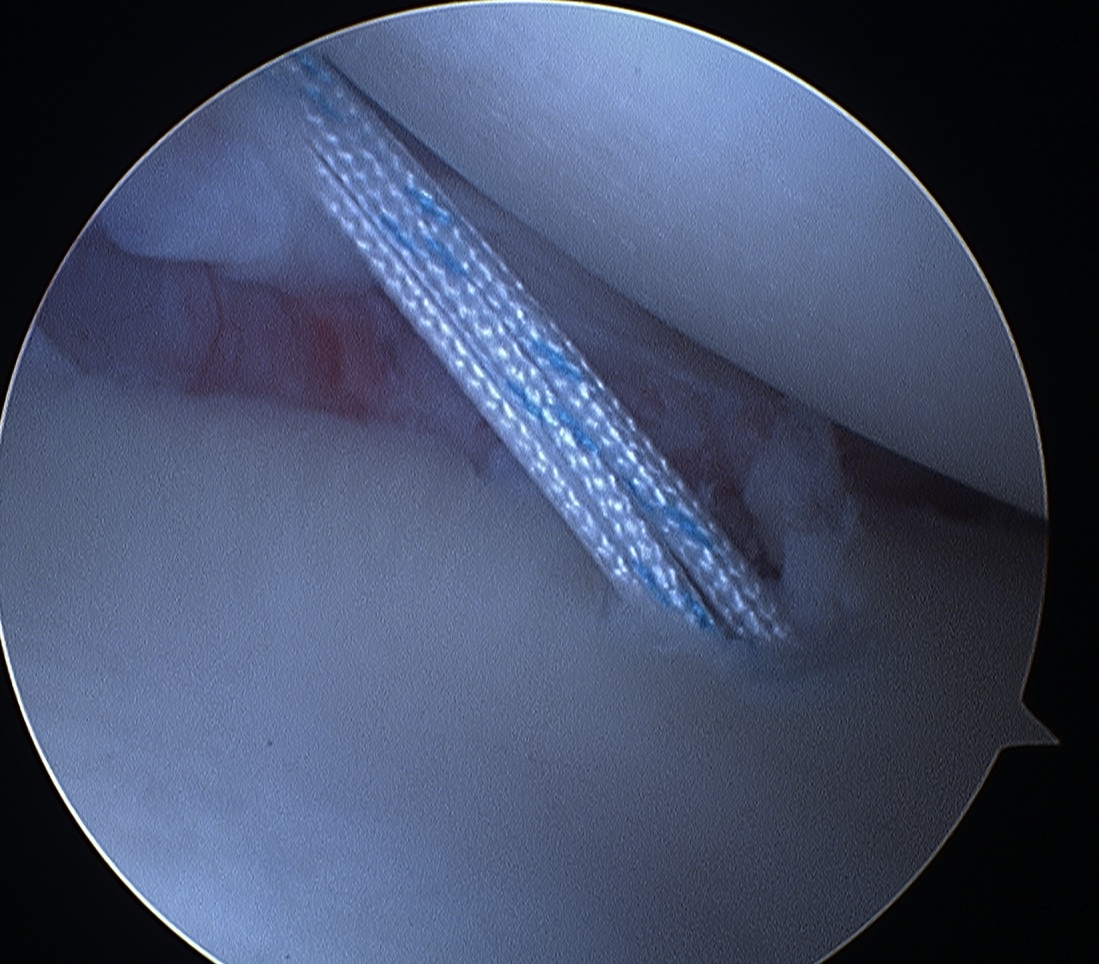

Insert anchors

Inferior anchor at 5.30 o'clock

- curved anchor guide / trans-subscapularis

- on rim of glenoid

Other anchors typically at 3 and 4 o'clock

Pass sutures and tie knots

Typically curved suture passers

Aim to tighten capsule medially and superiorly onto glenoid